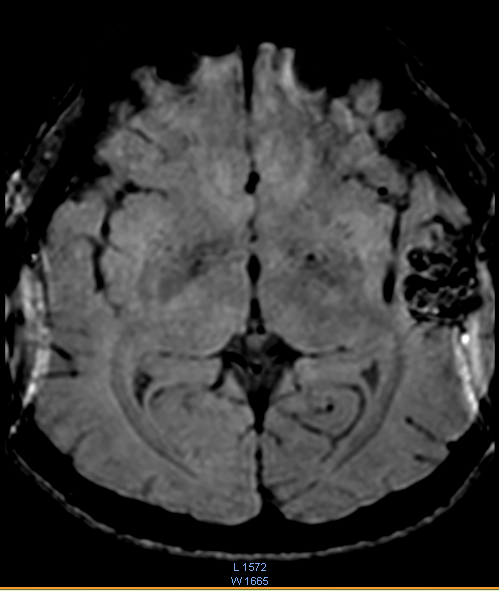

Khoa Chẩn đoán hình ảnh đã tiến hành chụp MRI sọ não với các xung MRA, MRV, dựng hình mạch máu não. Kết quả cho thấy, Bệnh nhân bị dị dạng mạch máu não (AVM) vùng thái dương bên trái có nguồn cung cấp máu từ động mạch não giữa cùng bên (bên trái), tĩnh mạch hồi lưu về xoang tĩnh mạch bên (bên trái).

Hình ảnh tổn thương

VEM BOLD

MRV